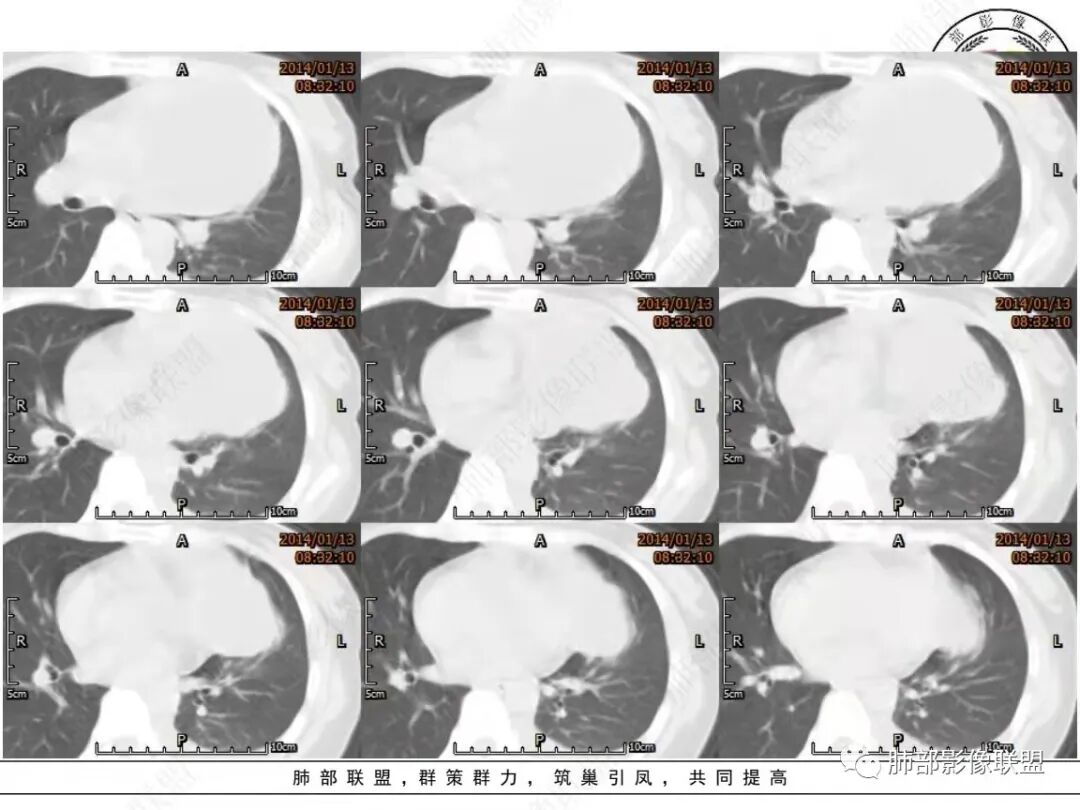

(5)肿瘤的囊性区由于密度低,被周围组织环绕,增强扫描时可见壁的环形强化。

(7)CT有助于良恶性的鉴别:

①良性畸胎瘤,通常轮廓清晰、表面光滑,多呈囊性,多含油脂成分;

②恶性畸胎瘤,轮廓不清,边缘有毛刺,有时散在,多表现为实性肿块,较少含有脂肪成分。恶性肿瘤向周围脂肪浸润生长,増强扫描呈一过性显著强化。恶性畸胎可产生胸腔积液或心包积液,且逐渐增多。

典型畸胎瘤是含有多种组织的混合物,CT上有脂肪、软组织和钙化密度影,此种CT密度的多样性表现为畸胎瘤诊断提供了重要线索,并可借此与其他肿瘤进行鉴别诊断。

(1)典型的畸胎瘤可见脂肪、软组织和钙化等多种组织成分,钙化和脂肪成分是特征性的CT表现。

(2)皮样囊肿的囊壁显示较清晰。前纵隔的巨大囊性肿块,以畸胎瘤最为常见!